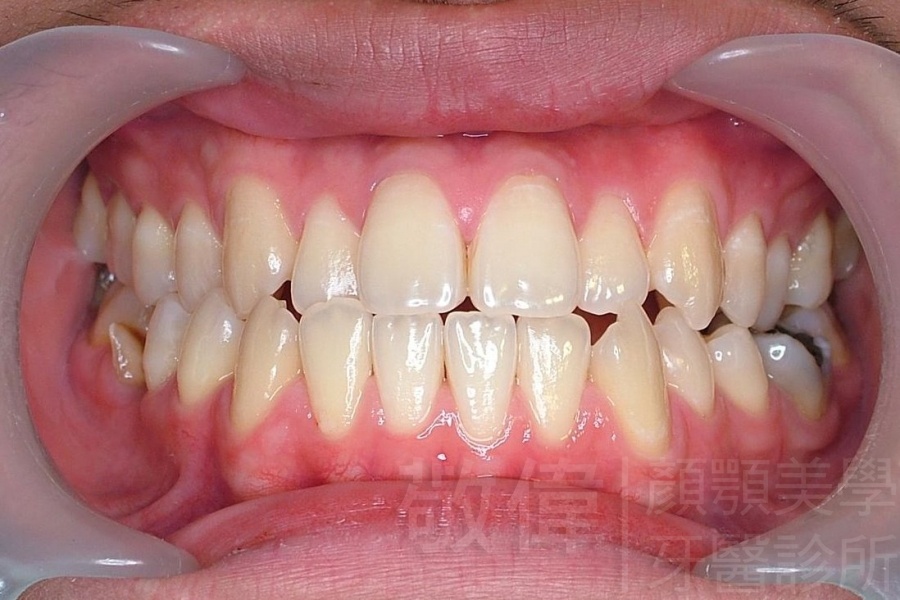

變臉矯正,原來戽斗妹跟大歪臉變成自信正妹

經由本院3D數影X光影像儀分析、與3D齒顎顏矯正技術,再配合口腔顎面正顎專科醫師施以正顎手術治療,雙方共同合作,使患者臉部外觀有很好的改善,大歪變小歪,產生了天南地北的大改變,她的人生也整個變得不一樣。

因為矯正與正顎手術的配合,使「戽斗妹」變成了「陽光正妹」,完全的改變了她的人生,在面對各種場合、與人交際都散發出自信微笑。所以,奉勸家長,如果小朋友有臉顎畸型的問題,應該考慮配合做這種簡單、安全、有效的正顎手術。